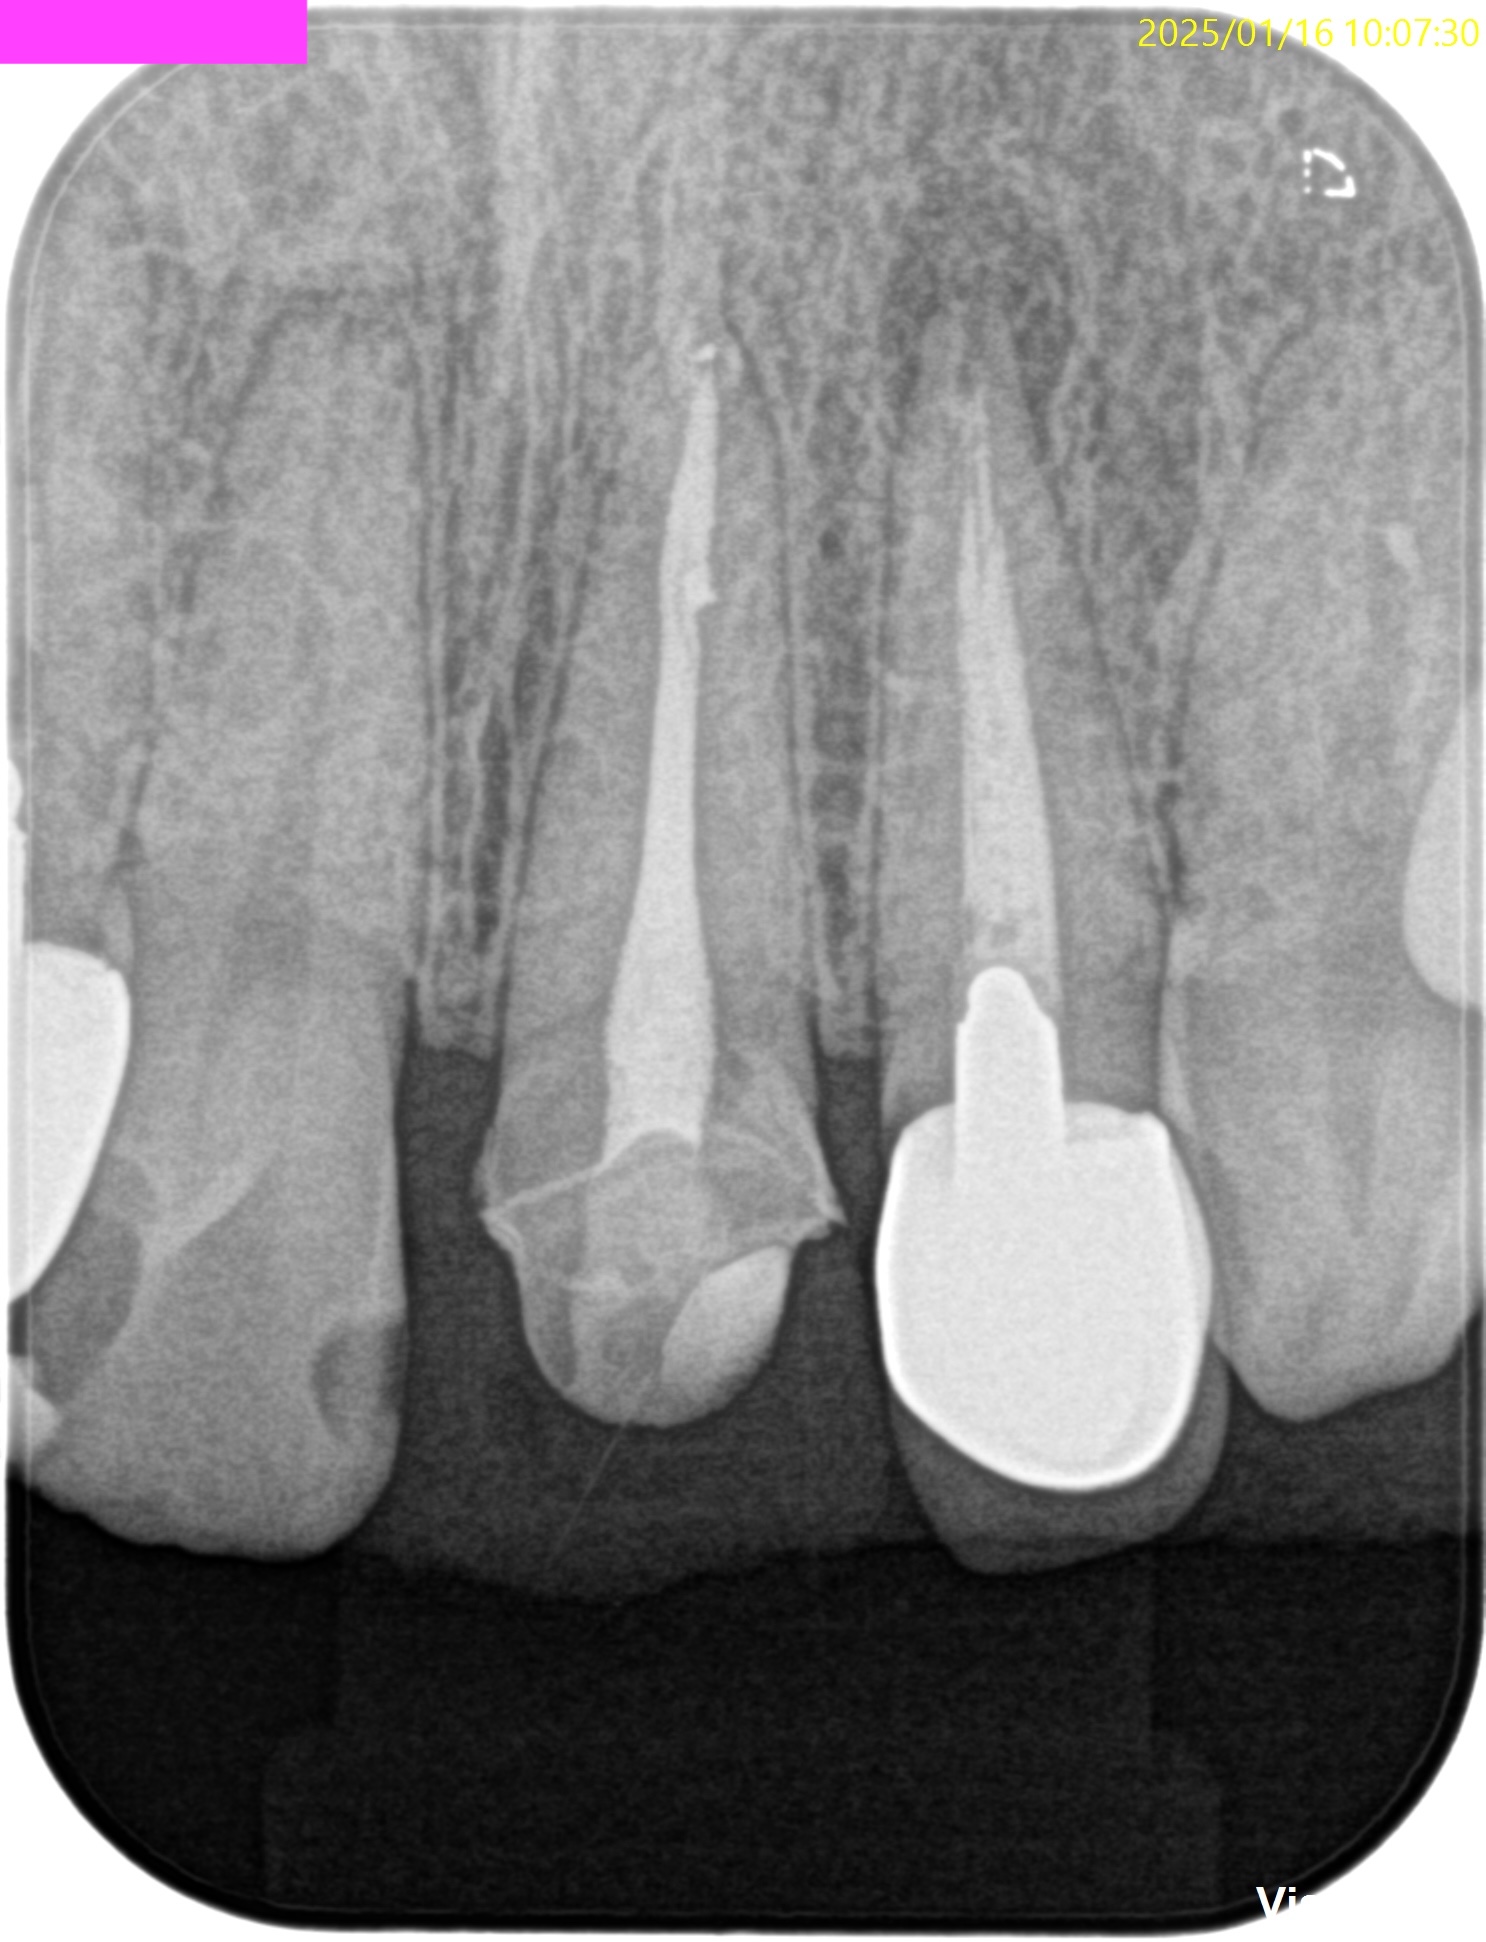

PA(2025.1.16)

#7,10はほぼ治療がなされていない。再根管治療が必要な案件だ。